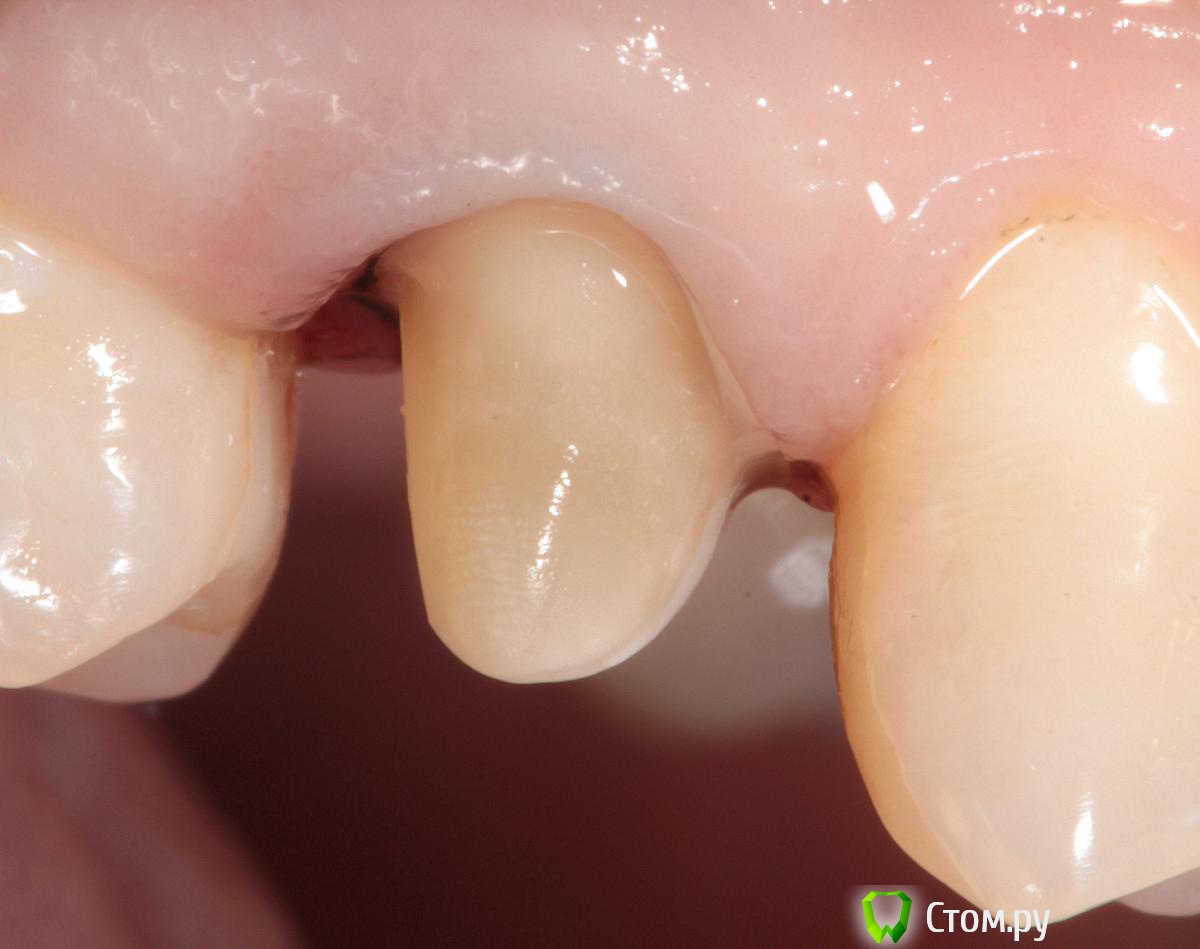

SDC Опубликовано 19 ноября, 2014 Поделиться Опубликовано 19 ноября, 2014 (изменено) Prettau, извините, не знаю, как редактировать название темы. Здравствуйте всем. В хирургическом много практиков, а по протетике - много теории)). Итак, разбавляю вино. (теория вечна)Протезирование премоляров коронками Преттау с нанесением керамики вестибулярно.Много фото, прошу прощения, поэтому без радикала, превью. Наверное даже так лучше, потому, что по клику откроются не сжатые фото, а радикал жмет.Протезирование в течение 2 недель. Фиксация на фуджи, без коффердама, но в сухих условиях (коффер не поставить по причине глубокий дистальной границы препарирования на обоих премолярах - глубокий кариес проксимальных поверхностей в анамнезе)Рг-контроль на предмет остатков цемента и на последнем фото удаленные излишки цемента на перчатке. Изменено 19 ноября, 2014 пользователем SDC 7 Ссылка на комментарий

SDC Опубликовано 20 ноября, 2014 Автор Поделиться Опубликовано 20 ноября, 2014 Отличный результат. Позвольте несколько вопросов.СВШ в боковых не ставите вообще,если да,то по какой причине?Как думаете антагонисты не будут истираться?Вы как-то меняете анатомию контакта при глубоких дефектах и недостатка сосочка?Спасибо.Спасибо Роман.По поводу штифтов. На самом деле, не имеет значения для меня.Важно, что не было титановых во фронтальном отделе (открываются при редукции тв.тк. небольшой объем композита вокруг штифта, что приводит к хрупкости билдапа и иногда металл.штифты светят через композит и керамику)Антагонисты истираться будут, а цирконий - нет. Что поделаешь.Сейчас мы с техником делаем нанесение вестибулярно и по скатам бугров, для уменьшения негативного эффекта повышенной прочности циркония и ускорения сдаваемости.контакт всегда площадочный, пятно контакта в корональной 1/4.Дефицит мягких тканей керамикой никогда не восполняем. Моделировка коронки максимально анатомична. Ссылка на комментарий